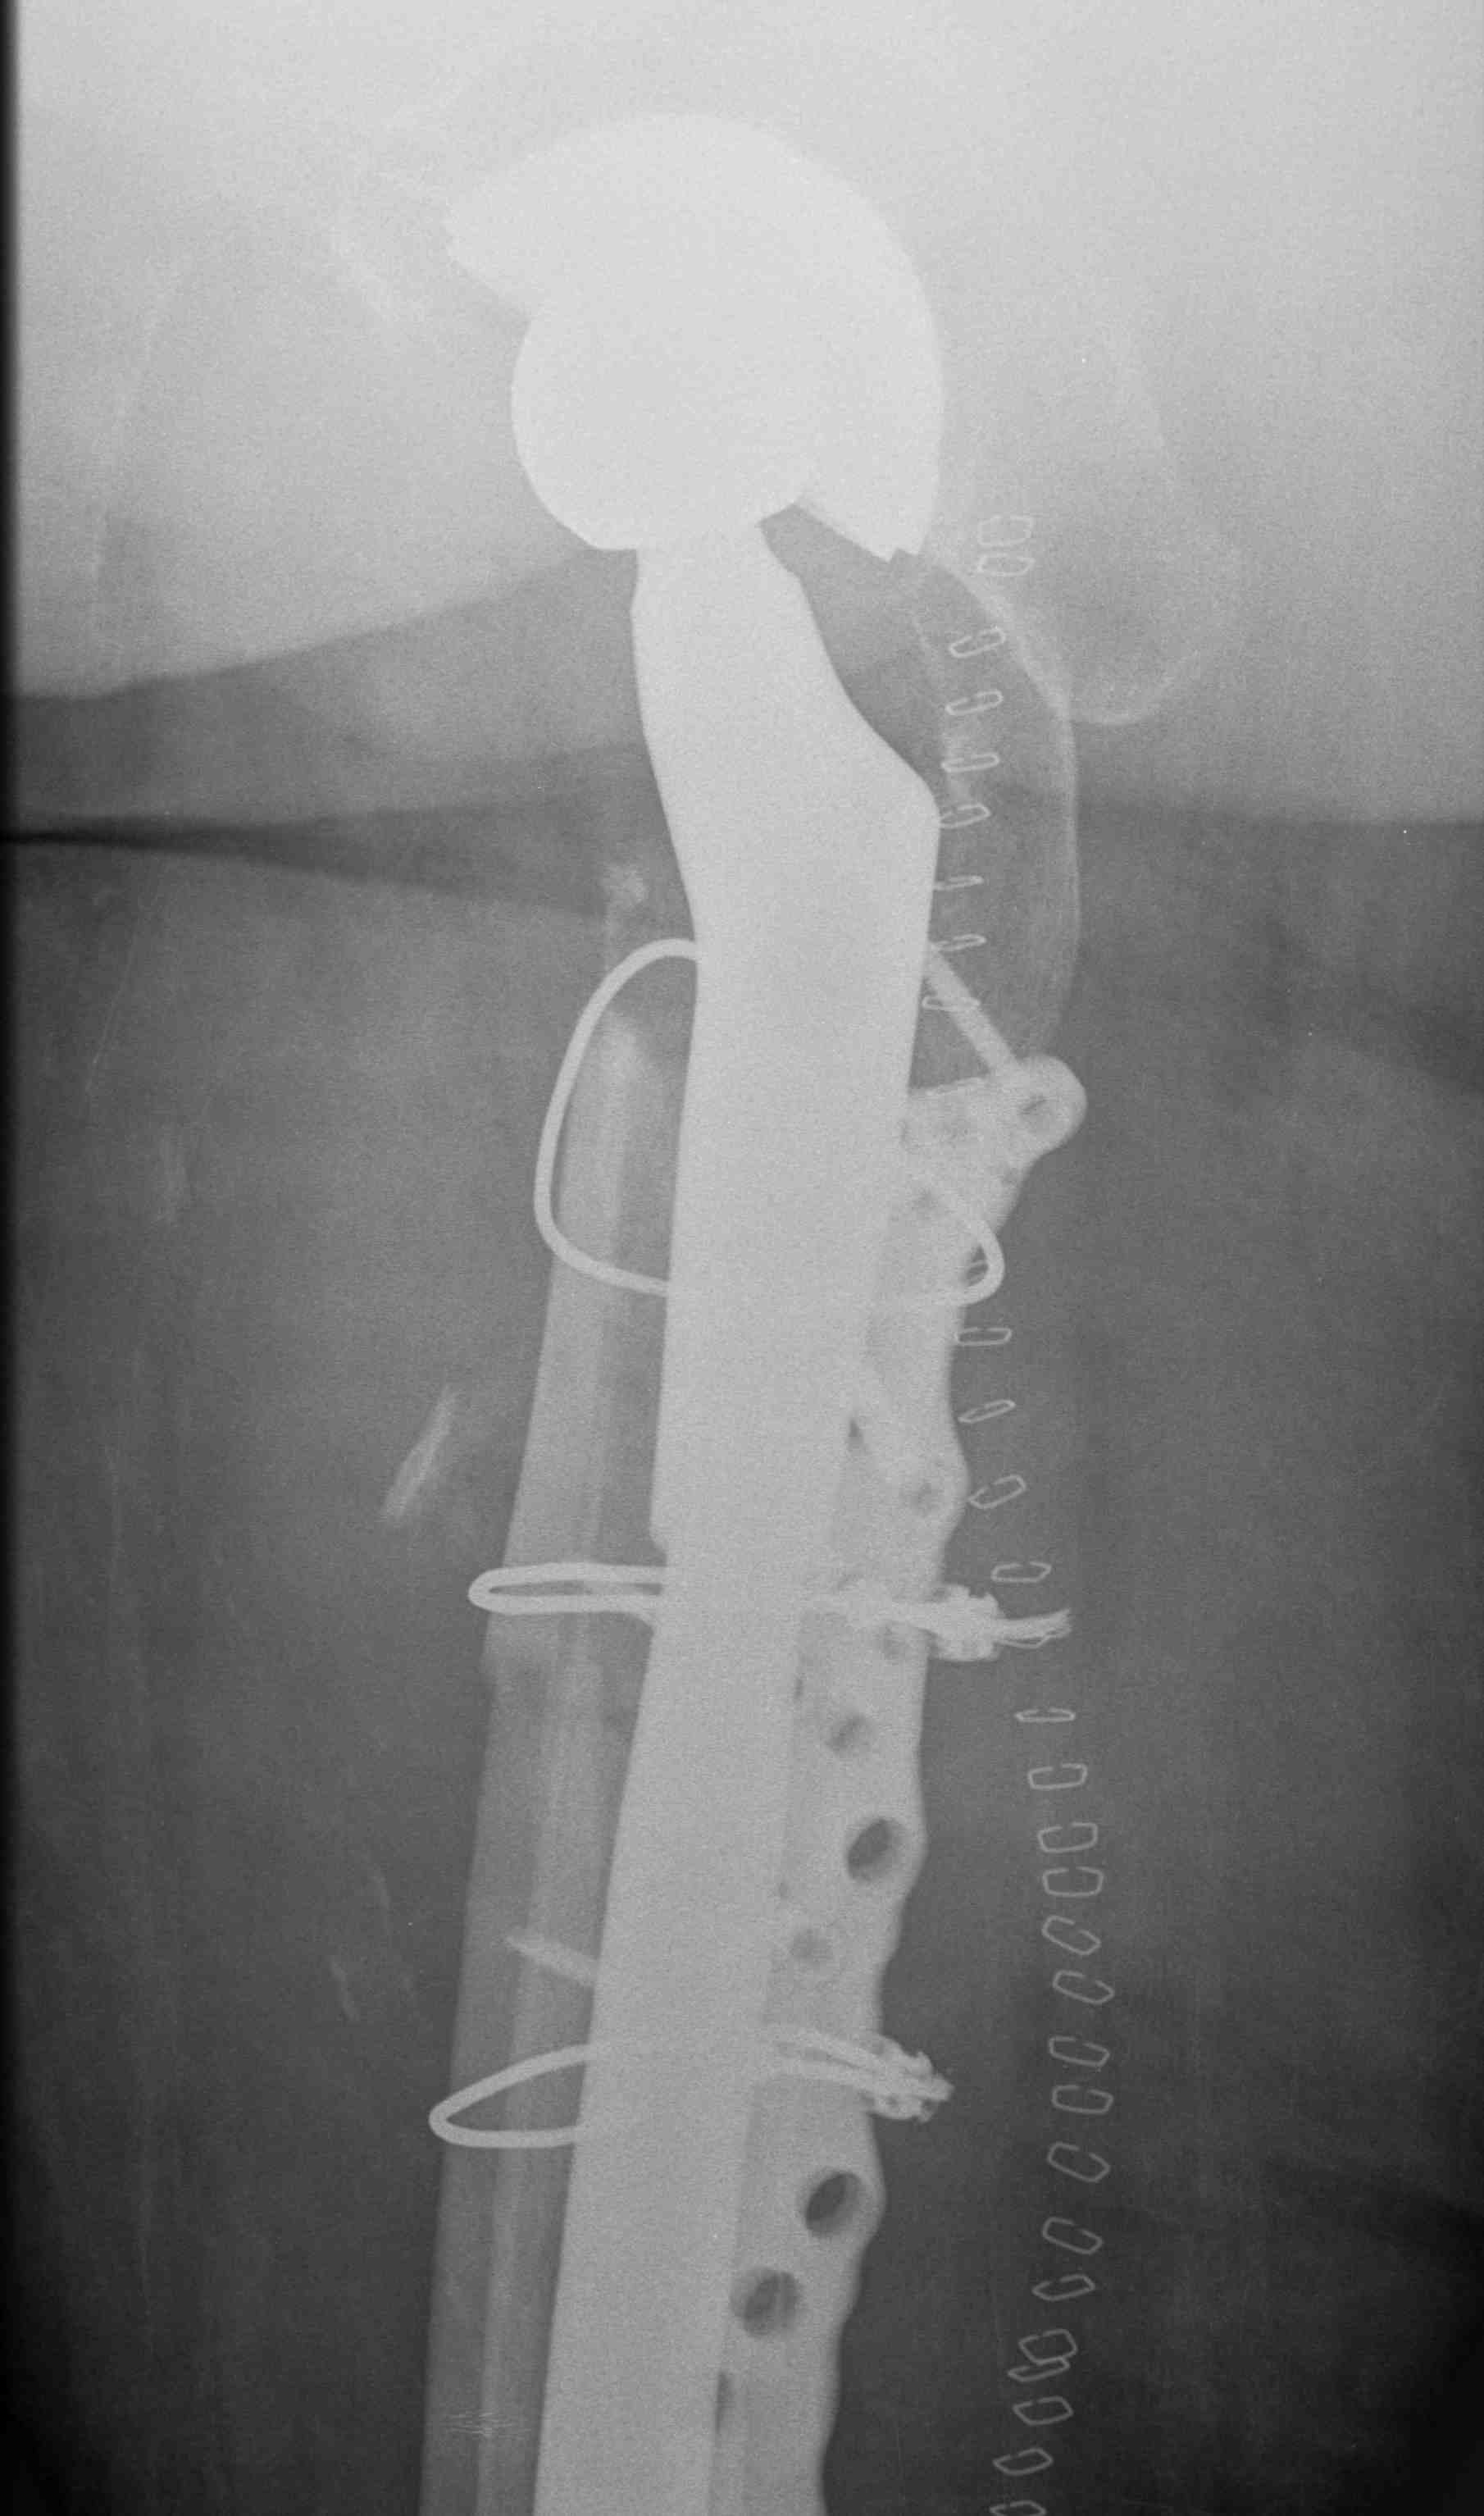

Long stem cemented revision

Long stem uncemented revision

Revision uncemented arthroplasty with Zimmer cable plate

Long stem uncemented revision with cortical strut allograft

Long stem uncemented revision with plate + cortical struts